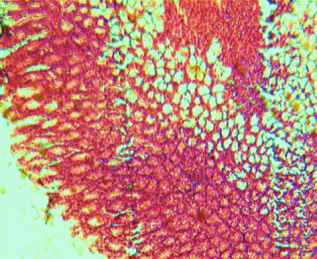

Histological evaluation of gastric lesion

Histological observation showed extensive damage of the gastric mucosa in the ulcer negative control group with necrotic lesions penetrating deeply into the mucosa accompanied by extensive edema and leucocyte infiltration of the submucosal layer (group 2).

Rats that received treatment with aqueous and methanol extracts of the leaves of D. thollonii had comparatively better protection of the gastric mucosa as seen by the reduction of ulcer area, reduced submucosal edema and leucocytes infiltration after 14 days of treatment (fig. 4).

Fig. 4: Histological study of acetic acid-induced gastric damage in rats

In fig. 4: (a’): histological section of a normal control rat: no injuries to the gastric mucosa are seen and the gastric wall is normal. ((b’): histological section of an ulcer negative control rat: there is severe destruction of the surface epithelium and necrotic lesions penetrating deeply into mucosa and submucosa layer. (c’): histological section of rats treated with Maalox (50 mg/kg): the gastric wall appears normally, but there is edema of mucosa and sub mucosa layer.(d’): the histological section of rats treated with Ranitidine (50 mg/kg): the gastric wall appears normally with all layers. (e’): the histological section of rats treated with 125 mg/kg of aqueous extract: there is mild disruption of the sub mucosal layer. (f’): histological section of rats treated with 250 mg/kg aqueous extract: there is moderate disruption of the surface epithelium. (g’): histological section of rats treated with 500 mg/kg of aqueous extract: there is mild disruption of the sub mucosal layer and edema of the muscle. (h’): histological section of rats treated with 125 mg/kg of methanol extracts: there is mild disruption of the epithelium surface and the sub mucosal layer and edema of the serosal layer. (i’): histological section of rats treated with 250 mg/kg of methanol extract: there is mild disruption of the epithelium surface and edema of the submucosal and serosal layers. (j’): histological section of rats treated with 500 mg/kg of methanol extract: there is moderate disruption of the epithelial surface although the gastric wall appears normally.